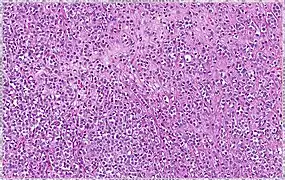

| Solid | 10% | Sheets of classical-appearing cells with little intervening stroma | |

| Alveolar | 5% | Aggregates of classical-appearing cells | |